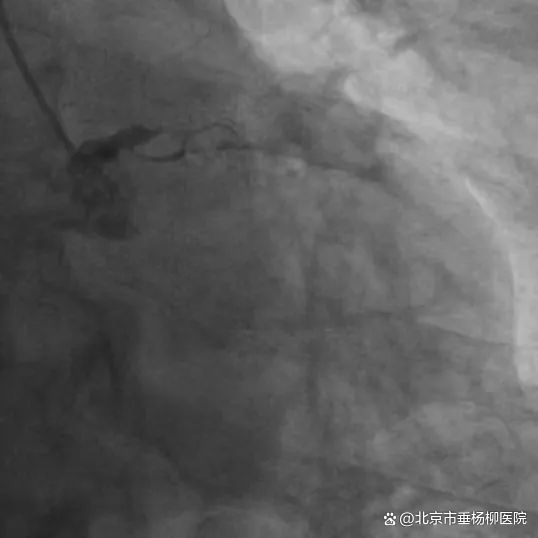

5月23日清晨,心内科主任医师胡江乔紧急会诊了这位67岁的急性广泛前壁心肌梗死患者,启动了胸痛绿色通道。心内科主任医师徐世莹、主治医师刘文博以最快的速度完成了冠脉造影检查,提示冠脉左主干100%闭塞。

左主干病变属于冠心病中的高危类型,一旦严重狭窄或闭塞,可能导致大面积心肌缺血或梗死,致死风险高,需及时诊断和治疗。开通左主干如同在心脏的“生命主干道”上拆除一枚随时可能引爆的炸弹,抢救成功率不足30%,是冠脉介入技术的天花板。

心内科主任医师包恩泽面对挑战,迎难而上,在主动脉球囊反搏(IABP)循环支持及在大量血管活性药物维持生命体征下,指引导管到位、导丝顺利通过病变到达血管远段,球囊扩张,支架植入。从患者到达医院急诊至IABP置入、血管开通,仅用73分钟。患者左主干至前降支顺利植入2枚支架,胸痛明显减轻,生命体征逐渐平稳。

▲支架植入前